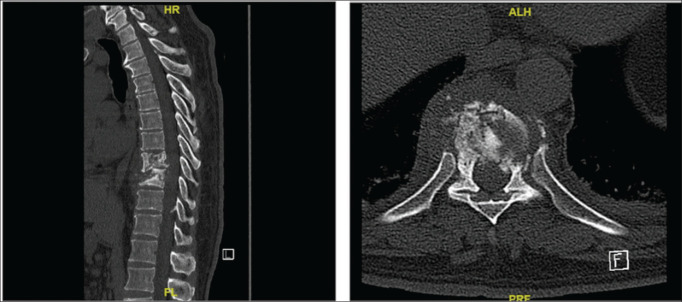

Results: In our analysis of 13 cases of Pott's disease, we observed a significant male predominance (69.23%) and diverse symptoms, with back pain (69.2%) being most prevalent among our patients. Lumbar involvement was the most frequently observed site (38.4%), and diagnoses were made through microbiology (69.2%) or clinical/radiological means (30.8%). Acid-fast bacilli (AFB) culture testing exhibited a positivity rate of 61.5%, while TB-PCR showed positive results in 57.1%. Imaging studies revealed vertebral lesions (90.9% CT, 81.8% MRI), abscesses (54.5% CT, 81.8% MRI), and spondylodiscitis (18.2% CT, 54.5% MRI). Treatment, administered in 92.3% of cases, involved the use of Isoniazid, Rifampicin, and Ethambutol. Surgical interventions, though less frequent, encompassed various procedures. Outcomes demonstrated a notable high cure rate of 84.9%, with a 15.4% incidence of cases experiencing loss of follow-up.